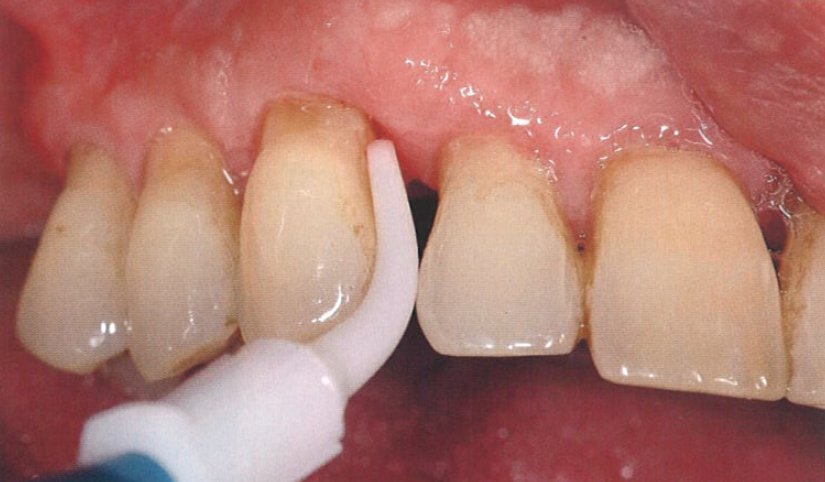

对于牙周炎治疗后的维护,其关键因素仍然是患者的家庭护理水平。医师必须抓住一切机会鼓励患者使用最合适的家庭护理方法。邻间隙宽大的情况不适合使用牙线,因为即使它能很好地清洁邻间隙,但并不适合清洁上颌前磨牙近中根面凹陷处的生物膜。在这种情况下,最好使用牙间隙刷,特别是一种具有特殊解剖形状的邻间隙刷(图12)。

口腔激光怎么治疗“难治性”牙周炎的激光辅助治疗_https://www.jmylbn.com_新闻资讯_第16张

图12  加强家庭护理技术,特别是对邻间隙的正常清洁至关重要